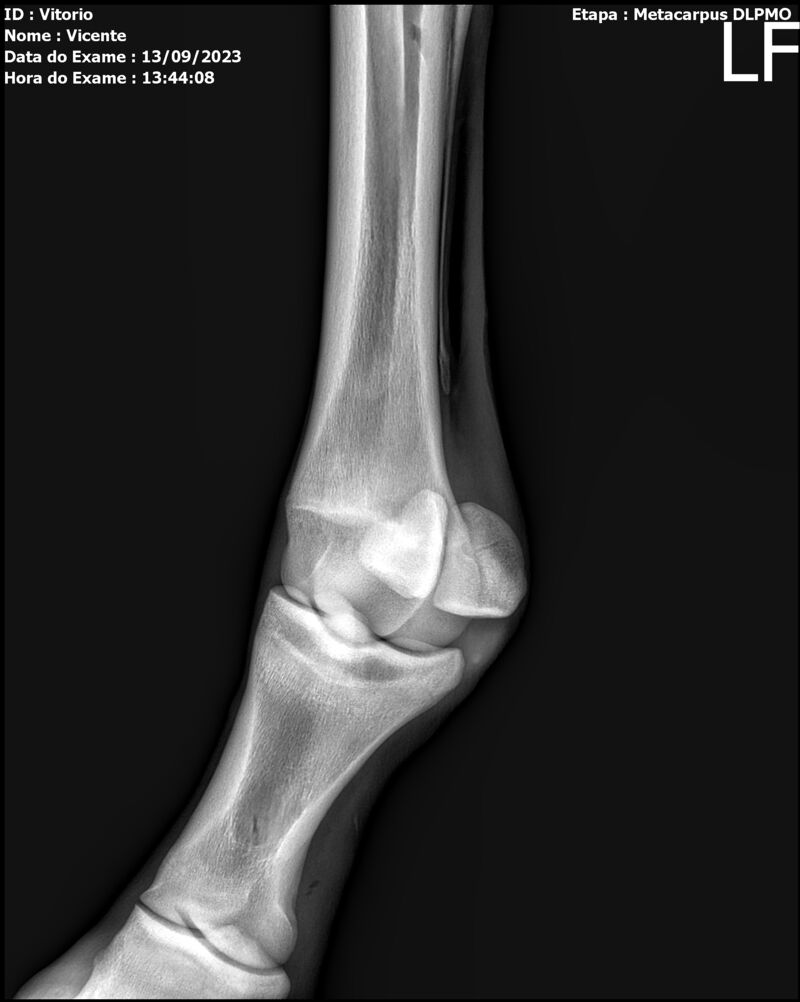

LOTE 13

THUNDER ZC

Raça: BRASILEIRO DE HIPISMO

Sexo: MACHO - POTRO

Nascimento: 17/09/2022

Altura Aproximada: 1,54

Pel.: CASTANHO

Registro: EM AND

Vend.: VICENTE CONTE

Local : PORTO FELIZ/SP